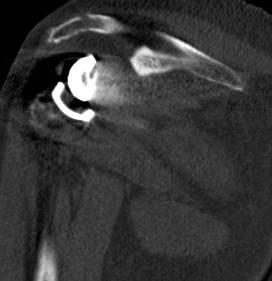

CT acromial stress fracturesCT Acromial Stress Fracture Reverse TSR

CT demonstrating acromial stress fracture